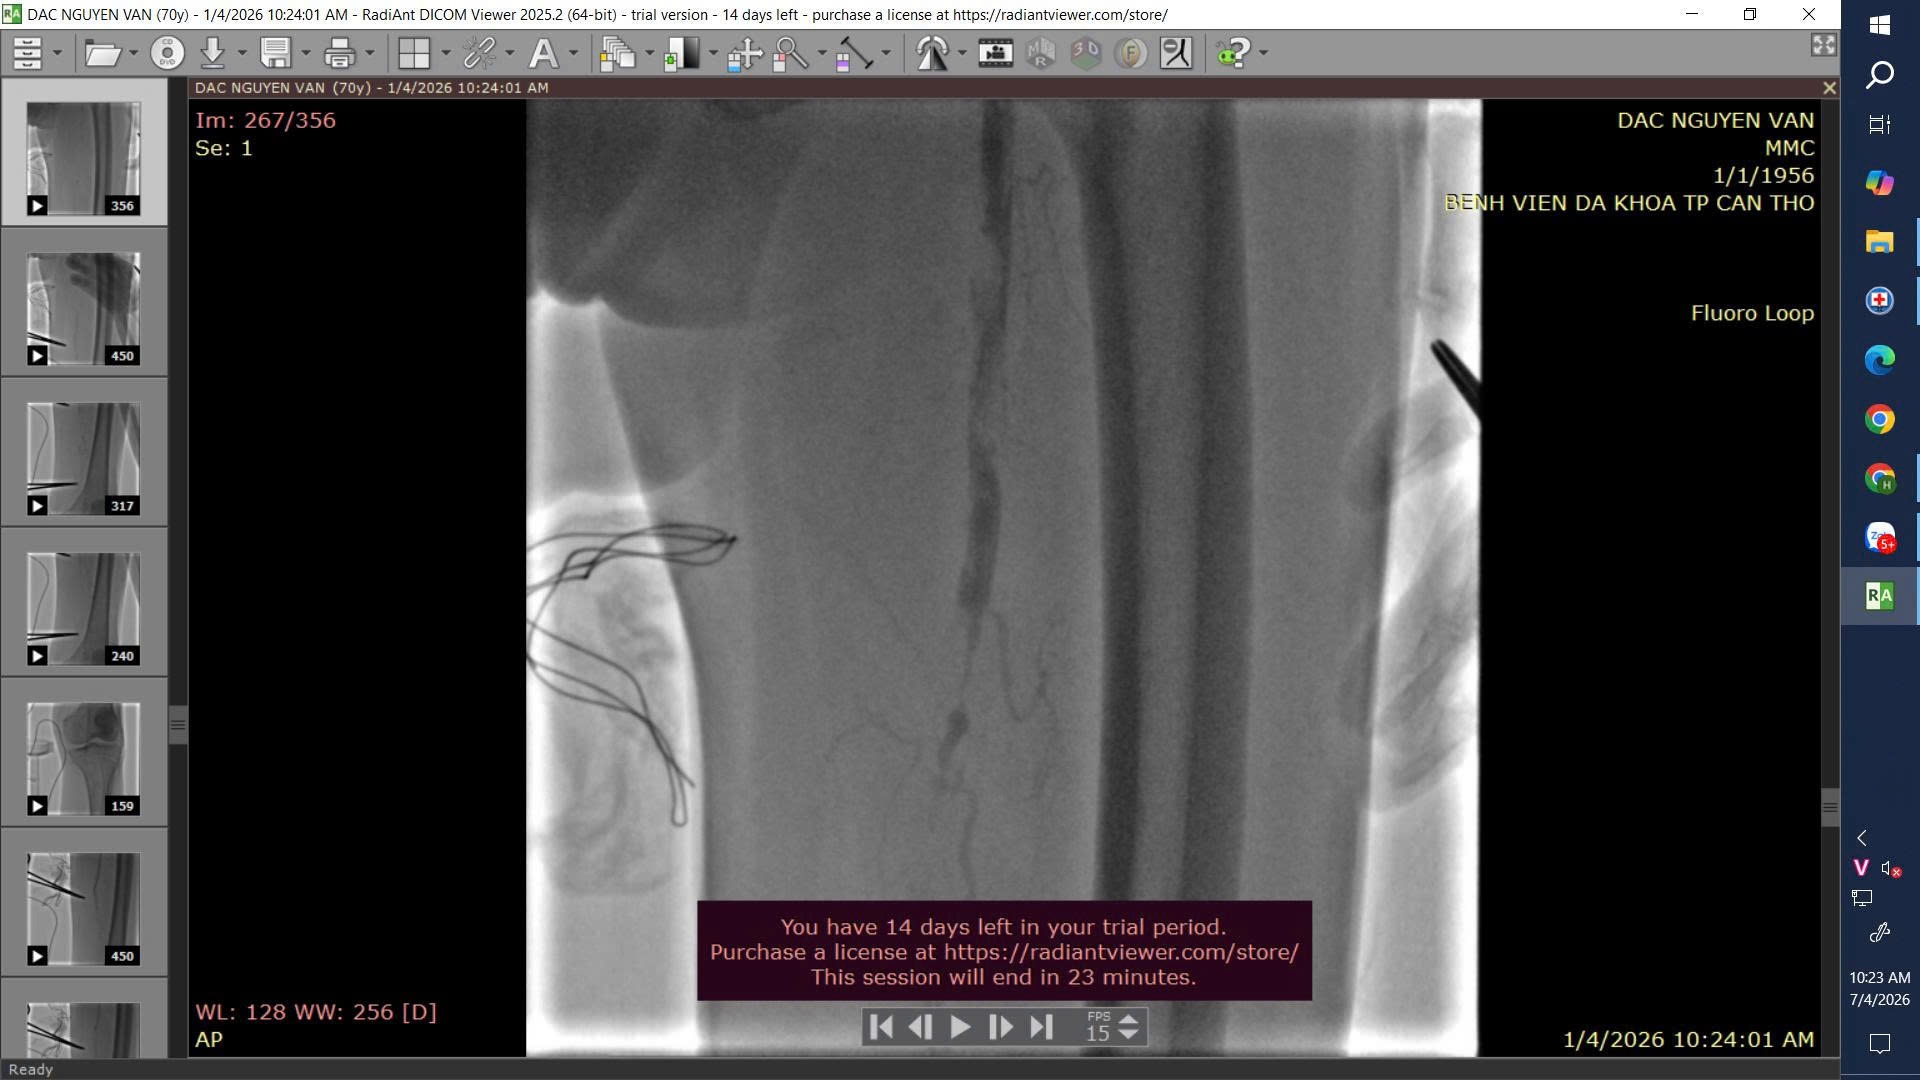

Trước tình trạng tổn thương phức tạp, ê-kíp Khoa Ngoại Lồng ngực đã tiến hành can thiệp nội mạch, nong bóng và đặt stent tại động mạch chậu trái, đồng thời tái thông động mạch đùi nông. Ca can thiệp diễn ra thành công, giúp khôi phục lưu thông máu cho chi dưới.